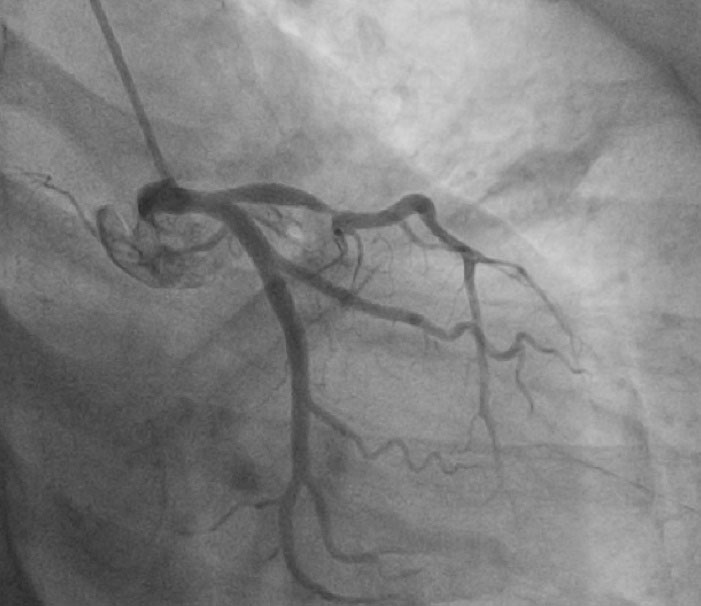

and show the echocardiographic image of GLPSS and Coronary angiography of same patient respectively.

Figure 5. Coronary angiography image (same patient image with echocardiography image shown).